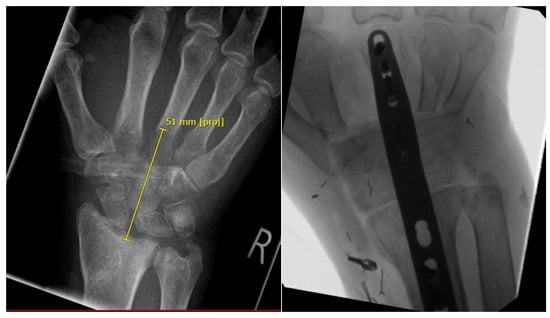

3.2.1. Arthrodesis of the Wrist with Vascularized Iliac Crest Bone

| GROUP 2 | Case 2 | Complete wrist, distal radius and proximal metacarpals | Osteomyelitis | 47 month | 64 | >5 cm | Vascularized iliac crest | Wrist arthrodesis | N/A N/A | 0-0-0° 50-0-35° | 50% | (N/A) | partial |